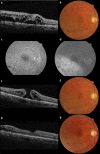

Case presentation: A 63-year-old Asian male was treated with intravitreal ranibizumab injection for chronic macular edema with branch retinal vein occlusion in his right eye. Before treatment, best-corrected visual acuity in his right eye was 20/200. Nine days after injection, a full thickness macular hole developed with reduction of macular edema. After pars plana vitrectomy combined with cataract surgery, the macular hole was successfully closed, and the best-corrected visual acuity in his right eye improved to 20/40.